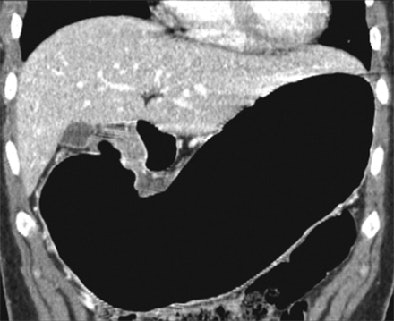

| Early gastric cancer in a 33-year-old woman. There is no identifiable gastric wall thickening on either the transverse CT scan (a, above) or the coronal MPR image (b, below). Virtual endoscopic image (c, bottom) shows a shallow depressed lesion with surrounding mucosal nodularity (arrows) in the angle of the stomach, suggesting early gastric cancer (T1). At histopathologic analysis, this lesion was diagnosed as type IIb + IIc early gastric cancer (pT1). Images used with permission of the Radiological Society of North America (Radiology 2005 Sep;236(3):879-85). |